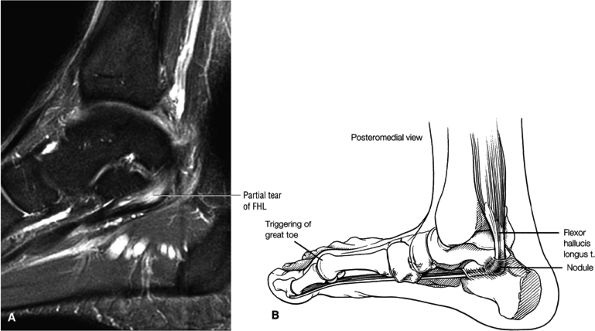

FIGURE 5.9 ● FLEXOR HALLUCIS LONGUS The flexor hallucis longus (FHL) flexes the great toe and plantarflexes the foot. The FHL is susceptible to injury during extremes of ankle plantarflexion and metatarsophalangeal dorsiflexion. The proximal sheath, 10 to 12 cm in length, has no mesotenon and may communicate with both the ankle joint and the sheaths of the flexor digitorum longus and tibialis posterior.

|